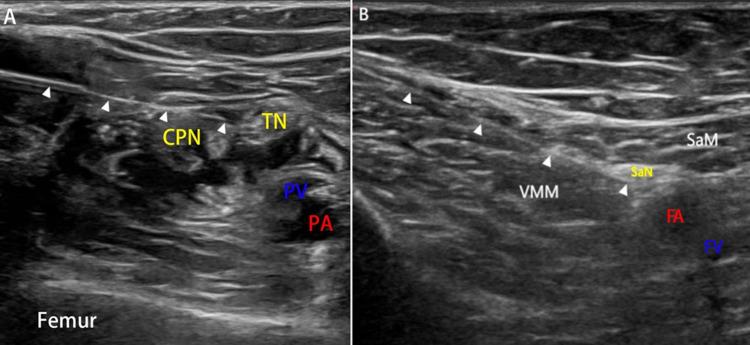

Peripheral nerve blocks are an important part of postoperative analgesia for the extremities. Previously, we reported that a single shot of 0.375% ropivacaine (20 mL) via ultrasound-guided popliteal sciatic and saphenous nerve blocks provided satisfactory analgesia after foot and ankle surgery; however, toe and ankle weakness in the early postoperative period became a concern for patients. Our preliminary data indicate that 0.25% ropivacaine may be effective for postoperative analgesia. Hence, we hypothesized that the analgesic effect of 0.25% ropivacaine would be noninferior to that of 0.375% ropivacaine at the same volume and would reduce the degree of weakness.

In this randomized, double-blind, self-paired, noninferiority trial, 31 patients who were scheduled for similar, elective, bilateral foot and ankle surgeries under general anesthesia combined with popliteal sciatic and saphenous nerve blocks were enrolled. Each patient was randomly assigned to receive 0.25% ropivacaine on one side and 0.375% ropivacaine on the other side. The primary outcome was the duration of analgesia, which was defined as the time from the end of the nerve blocks until the first sensation of pain in the surgical area, as indicated by a patient-reported visual analog scale (VAS) score ≥ 1. The secondary outcomes included static VAS scores, motor and sensory block grades, patient satisfaction scores, and the incidence of adverse effects.

外周神经阻滞是肢体术后镇痛的重要组成部分。此前,我们报道过经超声引导行腘窝坐骨神经和隐神经阻滞,单次注射0.375%罗哌卡因(20毫升)可为足踝手术后提供满意的镇痛效果;然而,术后早期出现的脚趾及踝关节无力成为患者关注的问题。我们的初步数据表明,0.25%罗哌卡因可能对术后镇痛有效。因此,我们推测,同等容量下0.25%罗哌卡因的镇痛效果不劣于0.375%罗哌卡因,且能减轻无力程度。

在这项随机、双盲、自身配对、非劣效性试验中,纳入了31例计划在全身麻醉联合腘窝坐骨神经和隐神经阻滞下进行类似择期双侧足踝手术的患者。每位患者随机分配在一侧接受0.25%罗哌卡因,另一侧接受0.375%罗哌卡因。主要结局指标为镇痛持续时间,定义为从神经阻滞结束至患者报告视觉模拟量表(VAS)评分≥1表明手术区域首次出现疼痛感觉的时间。次要结局指标包括静态VAS评分、运动和感觉阻滞分级、患者满意度评分以及不良反应发生率。